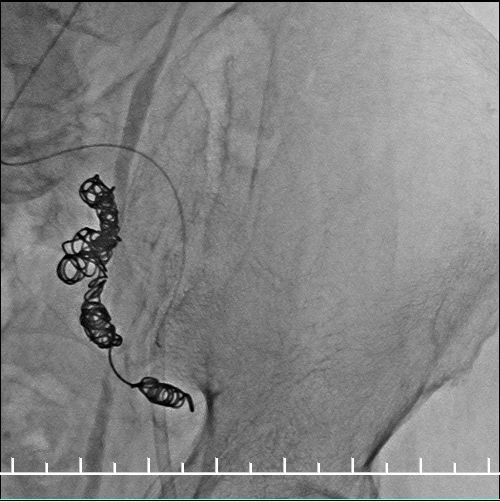

Ib型内漏(远端漏),需要处理

左右分别使用13.5*80、13.5*60mmFluency延长。左侧支架一定要越过髂动脉弯曲处,否则容易闭塞。此处可以看到左侧支架远端稍微有弯曲折叠。

仍然漏

不慌,还可以使用顺应性球囊扩张。

髂动脉硬化严重